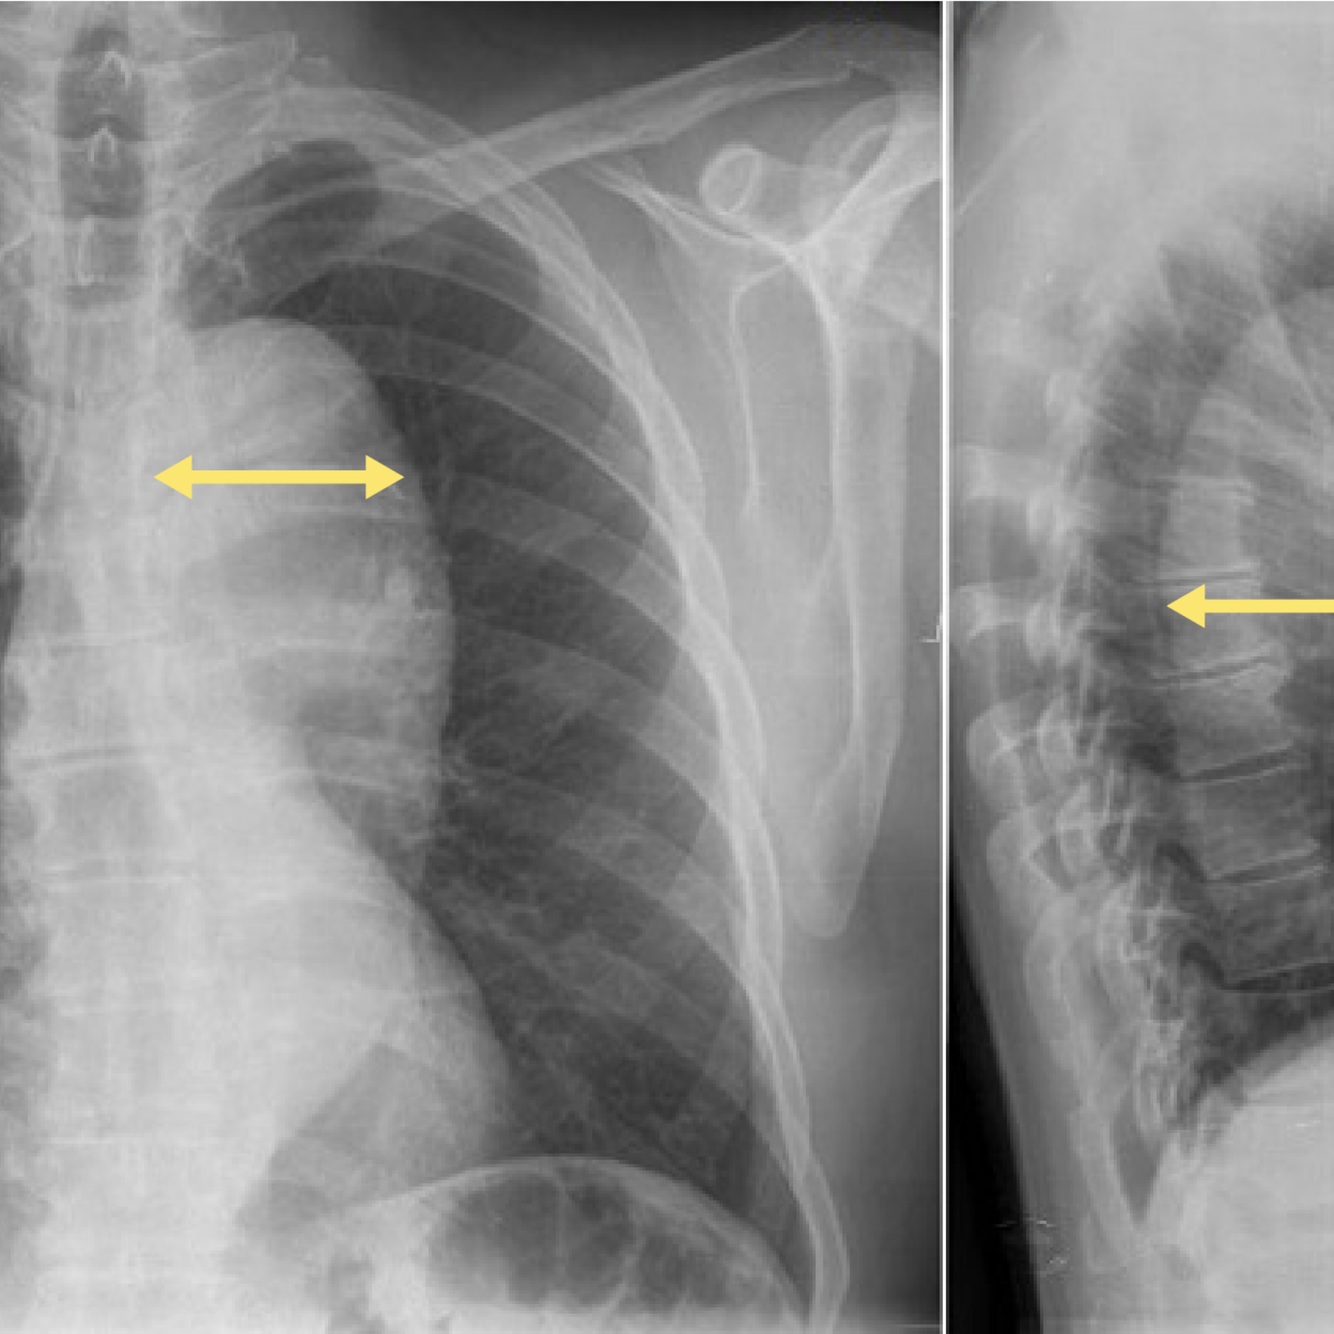

15

Q

A

How well did you know this?